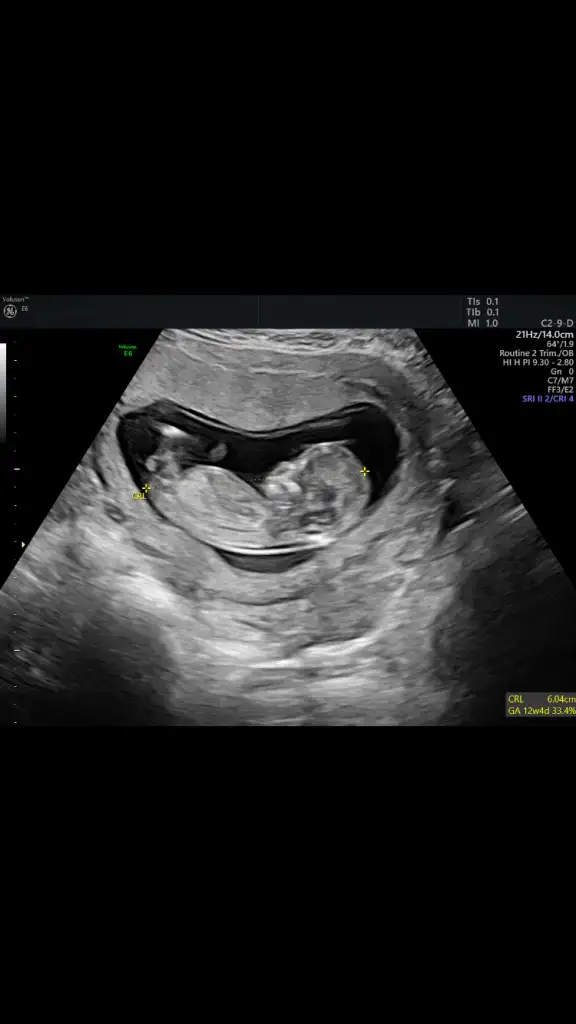

Daha önce 7+4 ken gondermisiz kiz gibi denilmis.Buna herkes erkek demis.Senin gibi.Buna göre erkek tabiki en iyi 11 12 13 haftalar olmalı

Bu iki haftanın farkı var mi?

Bu da 7+4 karından usg.

Sonradan gönderilen 7+4 olanlar.

7haftalik olan karin sabah vajinal öğlen çekilmiş.Saat farkı derken bunu demek iStedim.